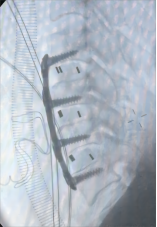

1.颈椎前路减压融合技术

颈椎前路减压融合术适用于①屈曲型颈椎骨折或骨折脱位所致的颈椎创伤性不稳定;②颈椎爆裂性骨折,椎体粉碎,压迫脊髓或脊髓前动脉,产生脊髓前综合征,需做前路减压,解除脊髓受压。③后路广泛性椎板切除,颈椎不稳,经后外侧融合仍不牢固。目前我科已成功开展前路ACDF技术、ACCF技术、ROI-C插片技术、Zero-P零切迹技术,具有创伤小、恢复快、疗效佳,早期下床活动的优点。